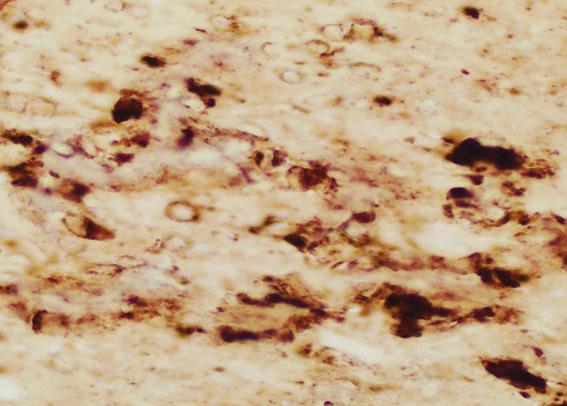

CJD is an incurable--and ultimately fatal--transmissible, neurodegenerative disorder in the family of prion diseases. Prion diseases originate when normally harmless prion protein molecules become abnormal and gather in clusters and filaments in the human body and brain. The reasons for this process are not fully understood. The accumulation of these clusters has been associated with tissue damage that leaves sponge-like holes in the brain. Human prion diseases include fatal insomnia; kuru; Gerstmann-Straussler-Scheinker syndrome; and variant, familial and sporadic CJD. Sporadic CJD is the most common human prion disease, affecting about one in one million people annually worldwide. Other prion diseases include scrapie in sheep; chronic wasting disease in deer, elk and moose; and bovine spongiform encephalopathy, or mad cow disease, in cattle.

Using a test for prion diseases known as Real-Time Quaking-Induced Conversion (RT-QuIC), scientists analyzed skin tissue from 38 patients--23 who had died from CJD, and 15 who died of other causes. They also collected brain tissue from the 23 CJD patients and from seven individuals who died of other causes. RT-QuIC correctly detected abnormal prion protein in each CJD patient sample tested and in none of the non-CJD group. The scientists noted that in the CJD group, the "seeding potential" for normal prion protein to convert to abnormal was 1,000 to 100,000 times lower in skin than brain tissue.

The scientists then exposed humanized laboratory mice to either brain or skin extracts from two of the CJD patients. All 12 mice inoculated with brain tissue developed prion disease, as did all 12 inoculated with skin extracts, though disease in the skin group took about twice as long--roughly 400 days--to develop. The group also reported that brain degeneration in both groups of infected mice was similar.